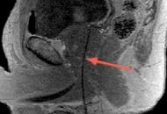

A special type of Magnetic Resonance Imaging (MRI) called multiparametric MRI (mpMRI) is used to plan, guide delivery, and confirm the effect of Focal Laser Ablation. Multiparametric MRI clearly characterizes a cancerous tumor within the prostate gland. It reveals the location, shape and extent of the tumor.

Once the target tumor is defined, the doctor can plan where to place the laser fiber in order to destroy the targeted area plus an extra safety margin. This planning includes the location and depth so the tip of the fiber is strategically placed to maximize the laser’s effect. Since the fiber is visible on MRI, the doctor knows that its placement is accurate.

The doctor can monitor the ablation as it occurs. When the laser is activated, the heat quickly expands with precise boundaries. Special MRI software called thermometry makes a temperature map of the prostate and the ablation. It shows the size and temperature of the laser-generated heat as it destroys the tumor and the safety margin. Thus, the doctor can avoid damage to nearby urinary and sexual structures, sparing normal prostate function.

When the ablation is complete, a final MRI scan is done to confirm that the targeted ablation matched the planned area. Also, multiparametric MRI can characterize the destroyed tissue, assuring there is no surviving cancer activity in the targeted area.